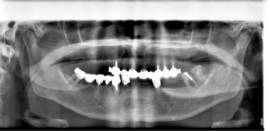

מתרפאה תושבת חוץ כבת 57 עם חוסר שיניים חלקי בשתי הלסתות. שאר השיניים הקיימות ניידות ואבודות , איכות הלעיסה ומראה החיוך ירודים מאוד.

בלסת העליונה ביצענו עקירות כל השיניים בישיבה אחת עם הרמות סינוס משני הצדדים והתקנת 11 שתלים. בפגישה נוספת עבור הלסת התחתונה נעקרו גם כן כל השיניים עם ביצוע מיידי של 10 שתלים.

מייד בתום ההשתלות בכל לסת בוצעה העמסה מיידית עם גשרי אקריל זמניים שהוכנו מראש וסיפקו מענה תפקודי ואסטטי מצויין לתקופת ההמתנה.

לאחר 6 חודשים וקליטת השתלים באופן מלא, קיבלה המתרפאה גשרי חרסינה קבועים ברמת דיוק ואסטטיקה מושלמים.